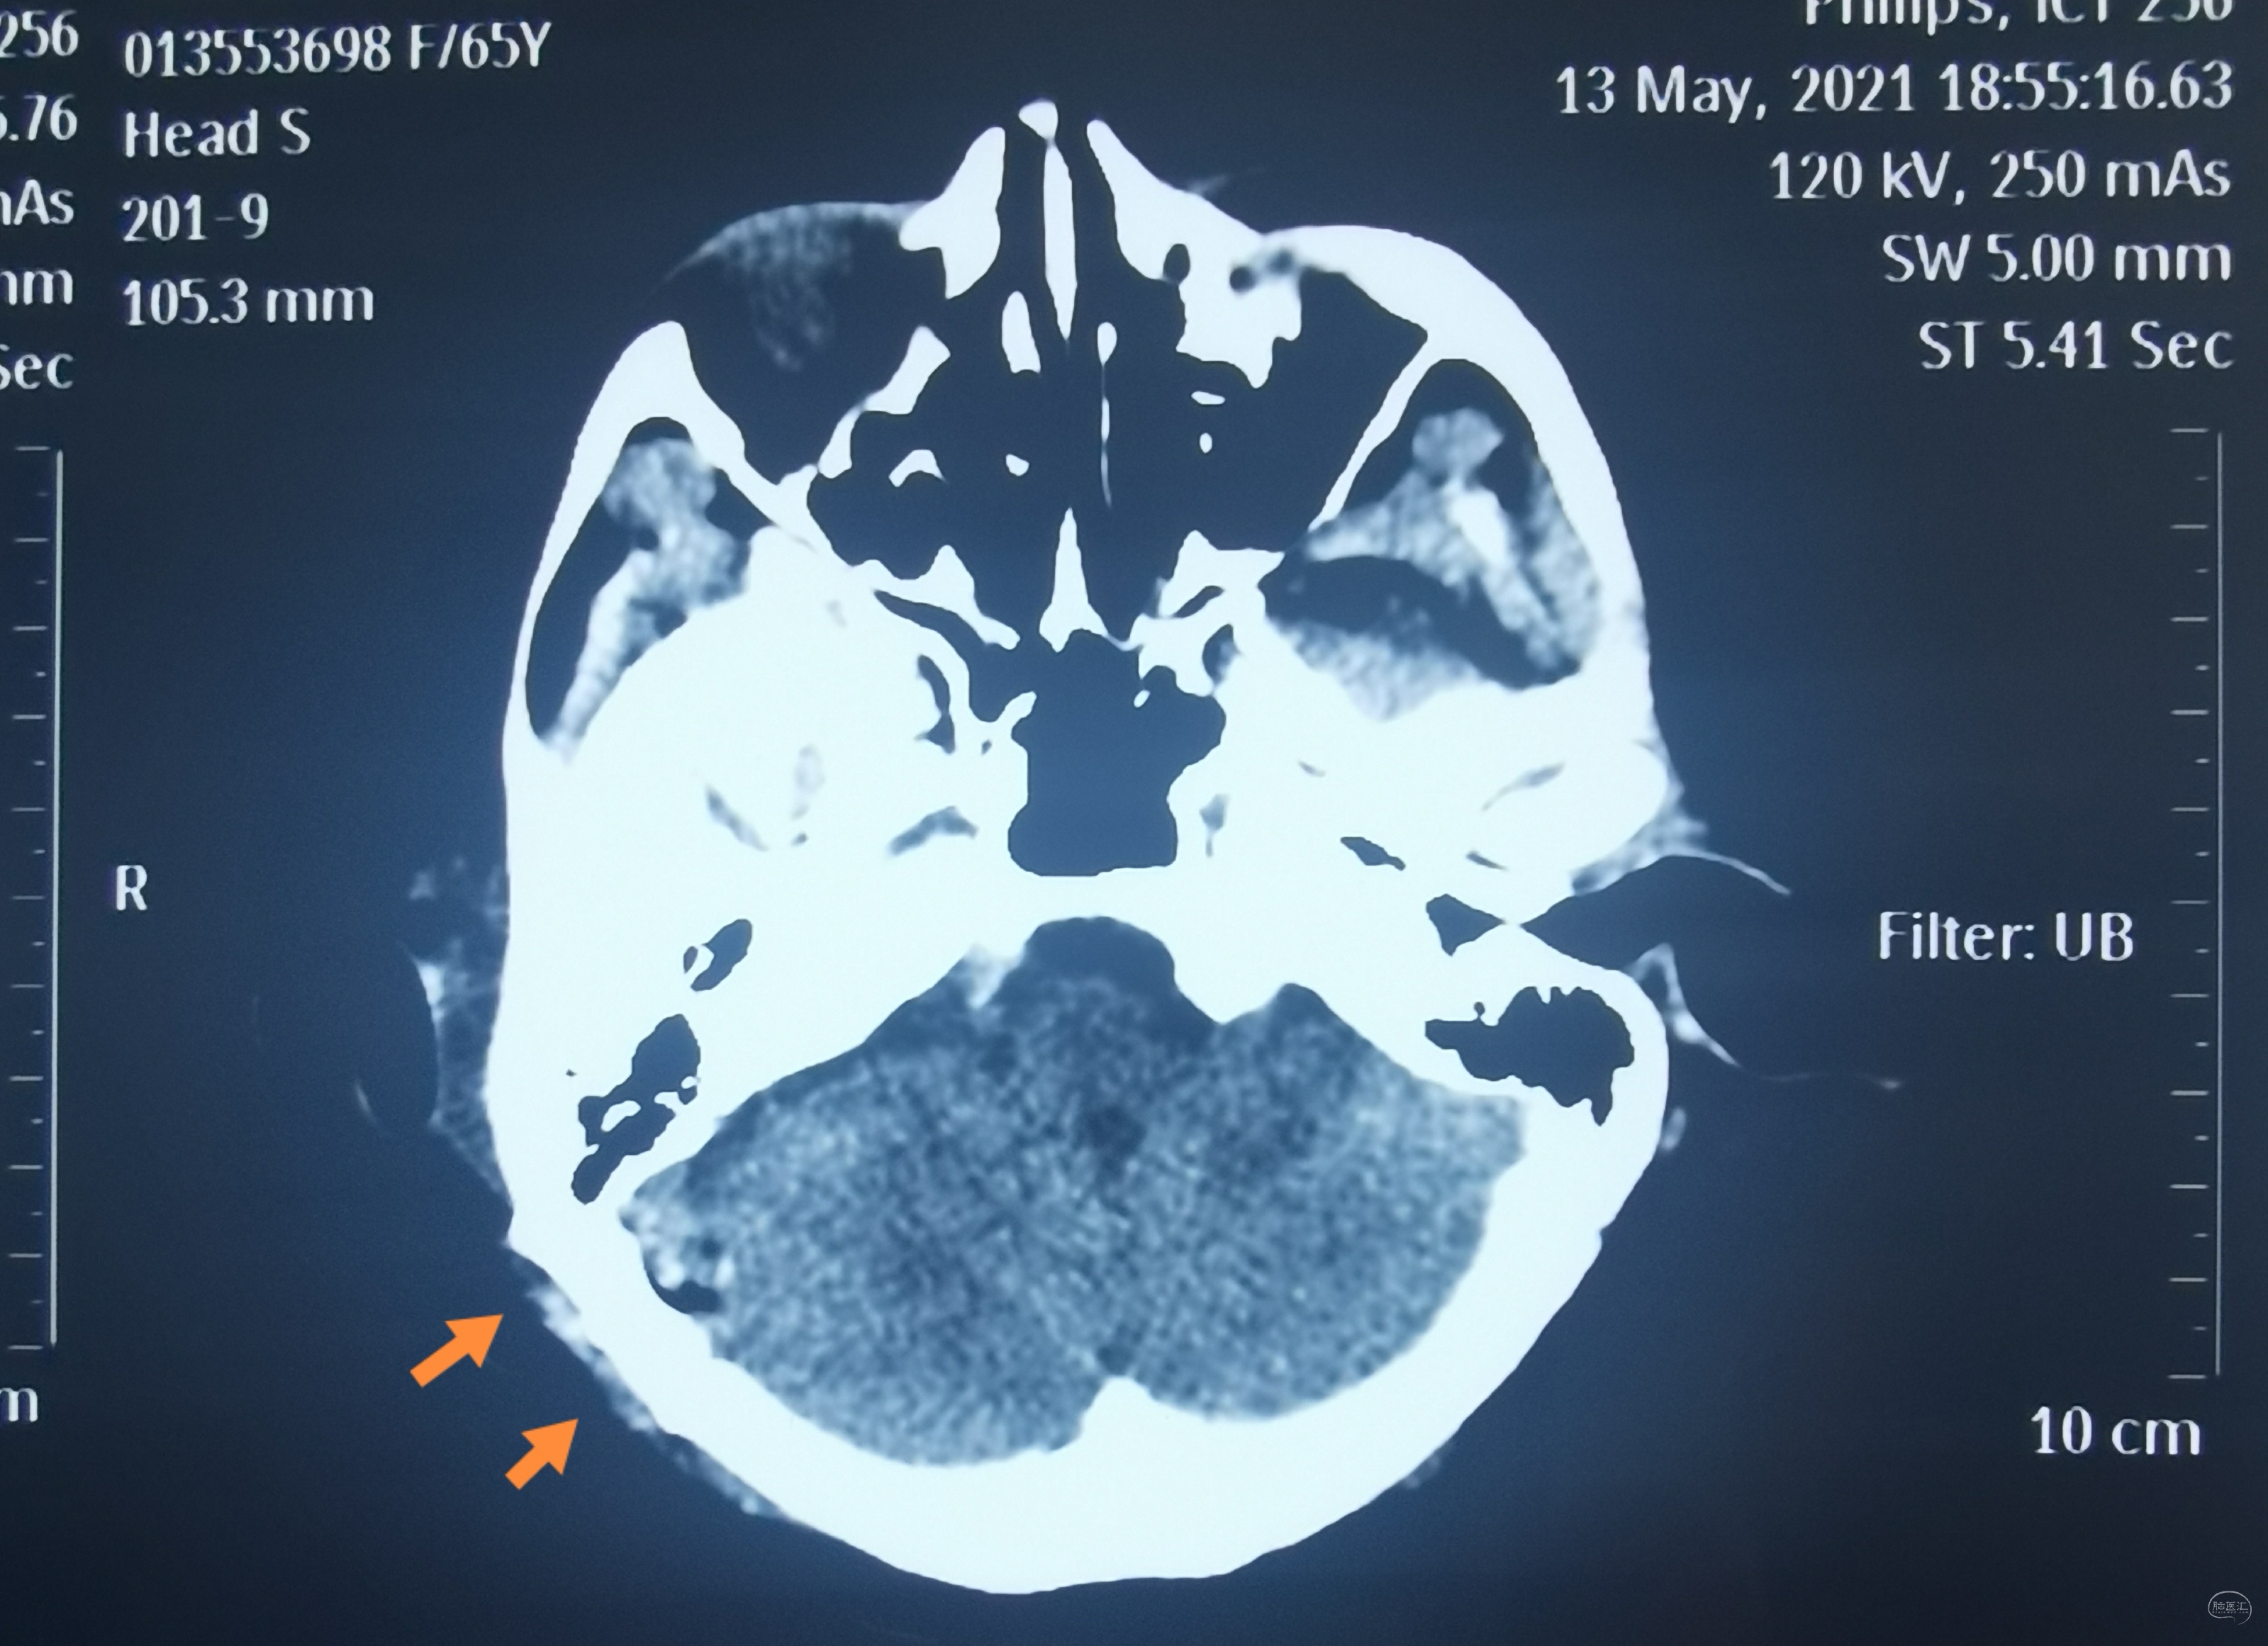

术后CT(骨窗直径约2.5厘米)